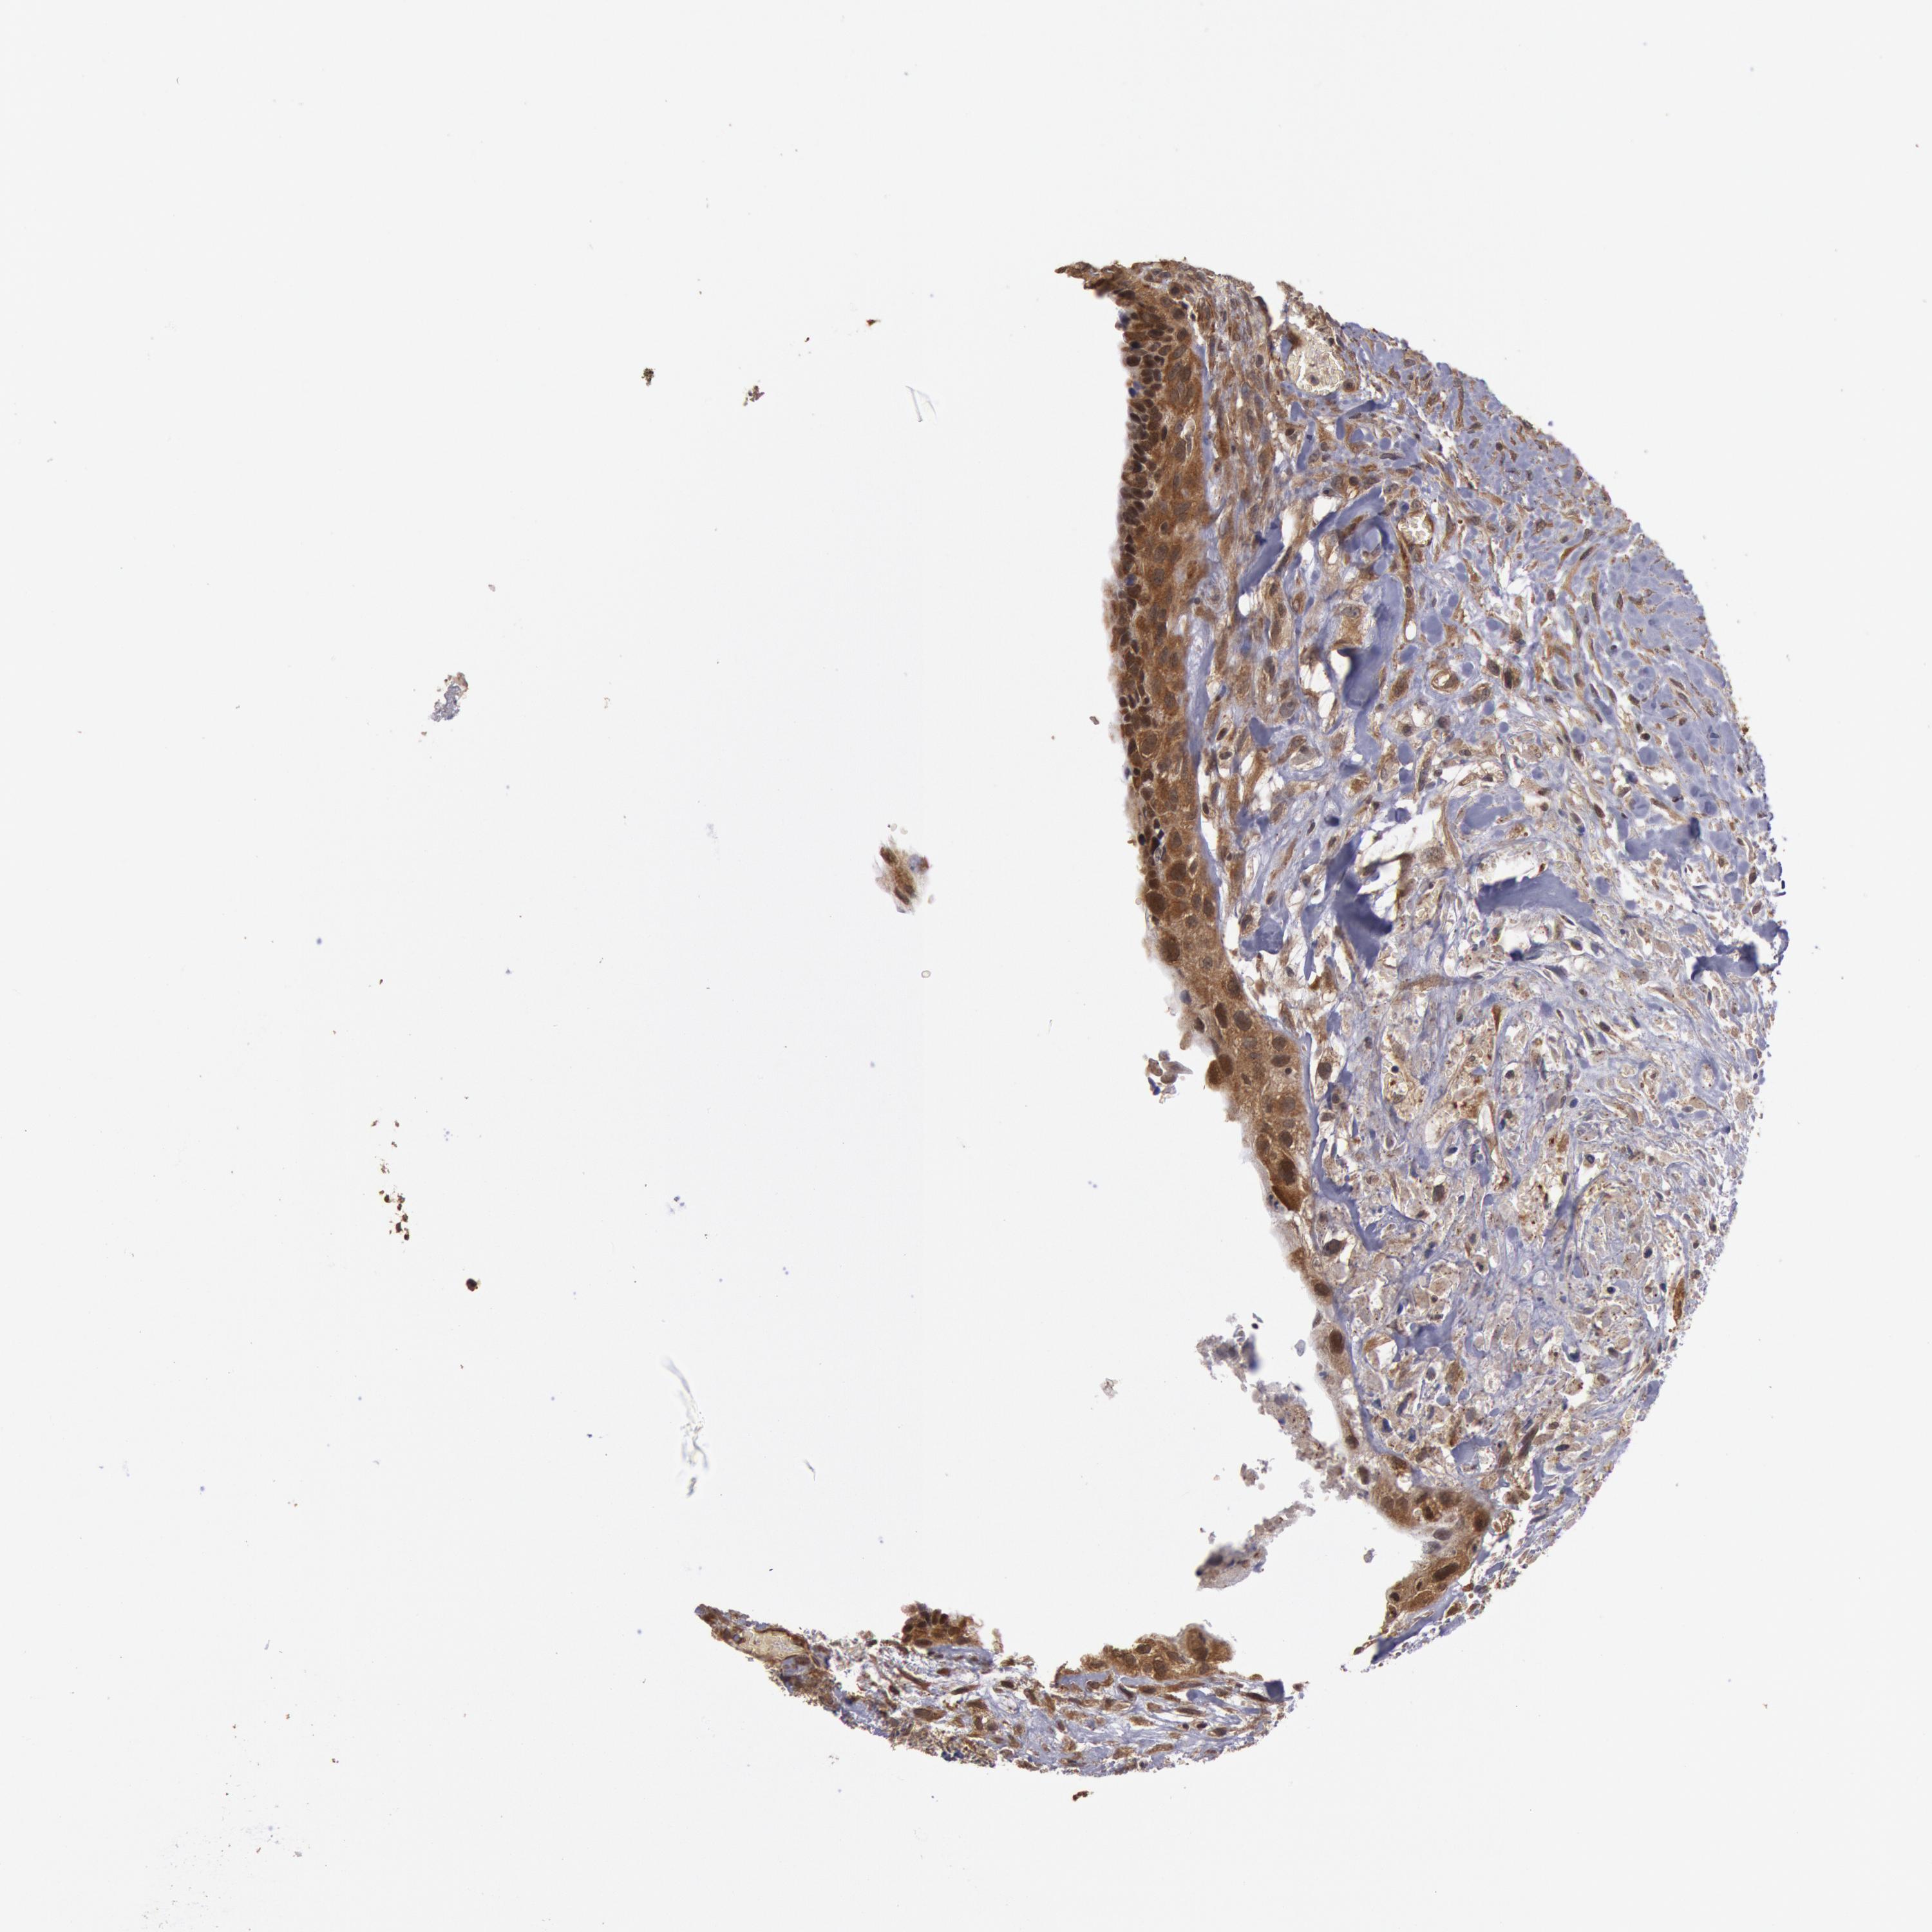

CANCER BREAST CANCER Show tissue menu

BRCA TCGA BRCA VALIDATION PROTEIN EXPRESSION

ANTIBODIES

AND

VALIDATION